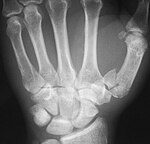

Bennett's fracture Edward Hallaran Bennett intra-articular fracture of base of Thumb metacarpal axial load along metacarpal in a partially flexed thumb Bennett's fracture at Who Named It? Bennett-Faktur seitlich cropped.jpg